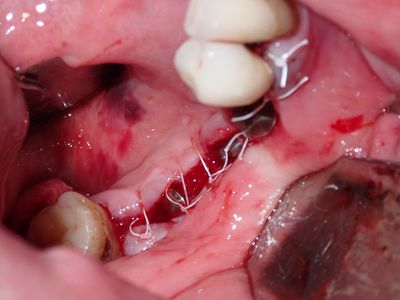

Bone loss noted, bone graft required, upon flapping, decided to place implants. Difficult case due to very strong macroglossic tongue, limited sulcular space. Short and wide implants placed, all socket/defects grafted with sticky bone from cortical allograft. membrane placed interimplant and fibrin membrane also used